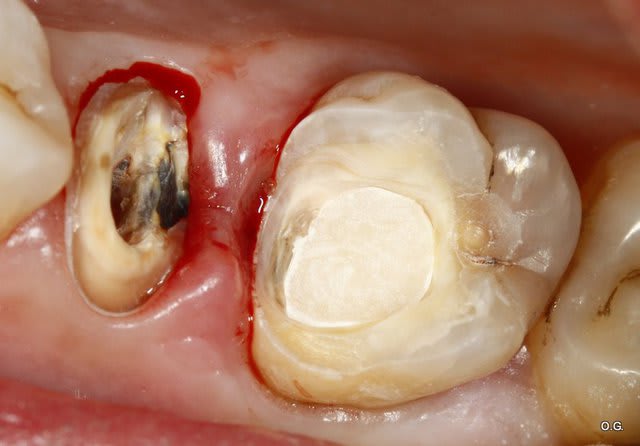

Bonjour que feriez vous sur cette 46 qui a été dépulpée correctement.

La patiente a 10 ans.

Le dentiste qui a fait l'endo veut faire un classique inlay core + CCM.

Perso j'aurais penché pour une reconsitution corono-radiculaire foulée et une couronne collée.

Je précise que l'image postée est pourrie car il s'agit de la fille d'une amie qui me demande conseille.

Son dentiste a refusé de lui envoyer la radio par mail et lui a donné une photocopie papier.